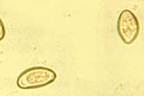

Для Opisthorchis felineus характерно продолговатое тело, заметно суживающиеся к переднему концу. Длину 8-13 ширина 1,2-2,5 мм. Специфический признак тАУ наличие 2 тАУ лопастных семенников расположенные наискось в задней части тела. Между ними проходит экскреторный канал S-образной формы. Петли матки расположены впереди семенников. Яйца мелкие 0,01-0,02 х 0,002-0,003 мм бледножелтого цвета, с нежной двухконтурной оболочкой, крышечкой на одном и бугорочном на противоположенном полюсе. Яйца при выходе наружу уже инвазионны т.к. содержат мирацидии.

Яйца Opisthorchis filineus

Основным является гельминтокопрологическое исследование. Яйца мелкие, размером 0,02-0,03*0,01-0,02 мм, желтоватые, с крышечкой и утолщением скорлупы на одном из концов. Можно использовать и иммунобиологические реакции. Через 10-20 мин после введения аллергена (0,1 мл внутрикожно в наружную поверхность ушной раковины) у заражённых животных образуется хорошо видимая и легко прощупываемая папула, 1,5-2 см в диаметре.